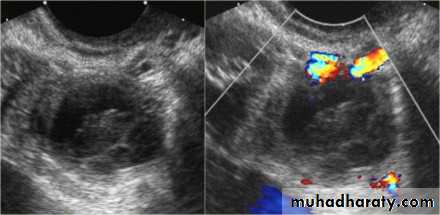

Ectopic pregnancy refers to the implantation of a fertilised ovum outside of the uterine cavity.

Radiographic features

Ultrasound

The ultrasound exam should be performed both transabdominally and transvaginally. The transabdominal component provides a wider overview of the abdomen, whereas a transvaginal scan is important for diagnostic sensitivity.

Positive sonographic findings include:

uterus

empty uterine cavity or no evidence of intrauterine pregnancy

Pseudo gestational sac or decidual cyst: may be seen in 10-20% of ectopic pregnancies

Direct visualization of the sac at the adenxia .